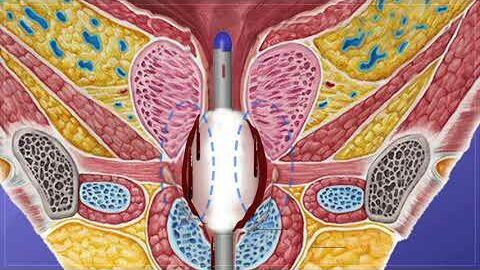

#255 A cost-effective model for training in Robot-Assisted Sacrocolpopexy- Dr. Yair Daykan